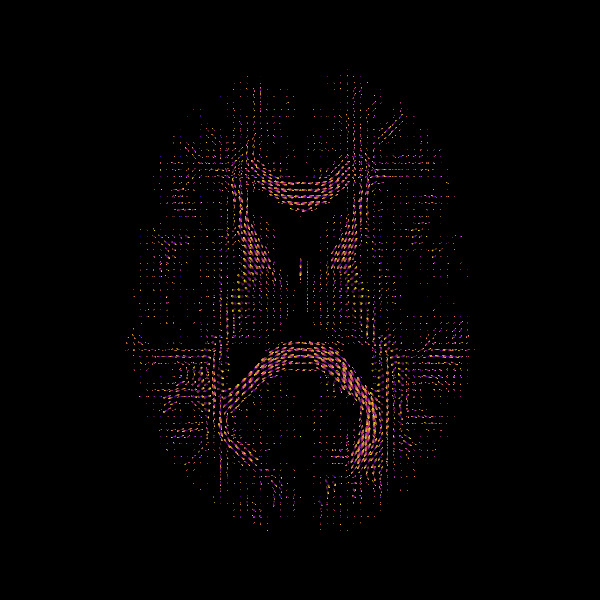

plt.matshow(np.rot90(ap[:, :, 10]), cmap=plt.cm.bone)

plt.savefig("anisotropic_power_map.png")

Anisotropic Power Map (Axial Slice)

The above figure is a visualization of the axial slice of the Anisotropic Power Map. It can be treated as a pseudo-T1 for classification purposes using the Hidden Markov Random Fields (HMRF) classifier, if the T1 image is not available.

As we can see from the shape of the Anisotropic Power Map, it is 3D and can

be used for tissue classification using HMRF. The

HMRF needs the specification of the number of classes. For the case of

MSMT-CSD the nclass parameter needs to be >=2. In our case, we set

it to 3: namely corticospinal fluid (csf), white matter (wm) and gray

matter (gm).